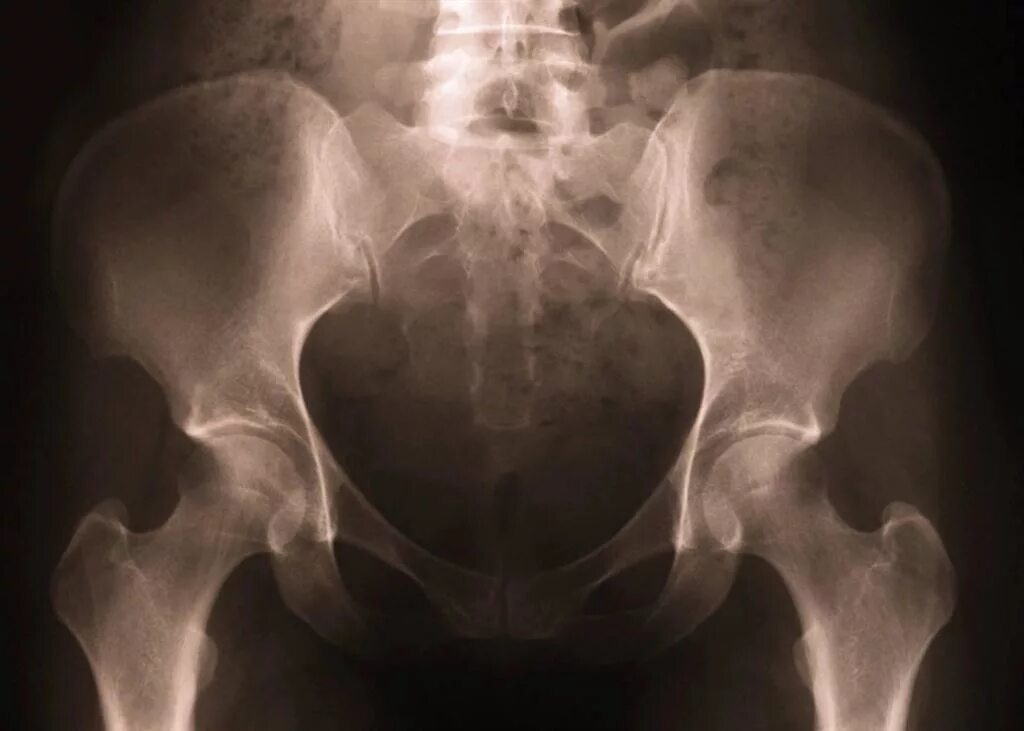

Снимок копчика